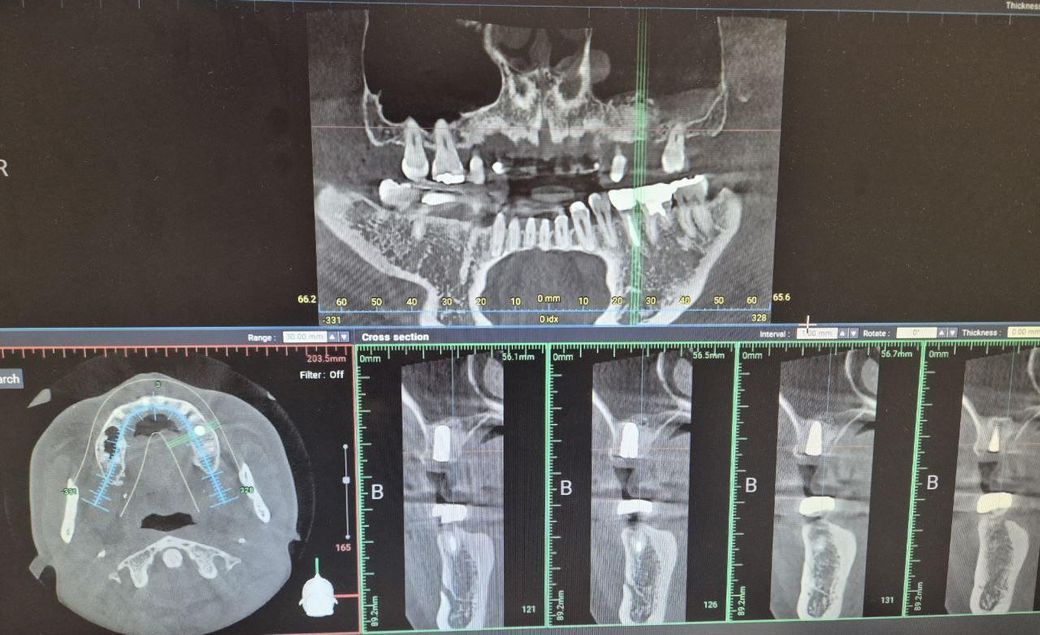

#26번 치아 2달 전 상악동거상술 + 임플란트 식립하였습니다.

기존 뼈 3~4mm 수직거상술로 10mm짜리 식립한 것으로 알고 있습니다.

수술한 치과에서 엑스레이, ct촬영하였는데 선생님은 뼈이식한 것은 문제가 없고 가벼운 상악동염 증상같다고 빨리

이비인후과 의원에 가니 이비인후과 ct가 더 정확하다고 해서 다시 촬영하였는데 상악동 염증이 없기 때문에

약을 줄수 없다고하십니다. 치아뿌리 쪽 점막 부은 것은 문제가 안되고 코이물감과는 상관이 없다고 해서 그냥 나왔습니다.

• 2번 째 사진

1. ct상으론 거상, 뼈이식, 식립 모두 양호하게 잘 된것 같습니다 술후 부종이 두달 가는건 흔치 않은데 감염 가능성도 고려해봐야 할 것 같습니다